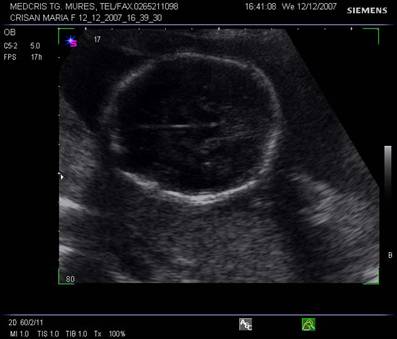

Rinichii - sectiunile transversale la nivel lombar fetal identifica retroperitoneal, cel mai devreme la 13 saptamani, de obicei la 17 saptamani, doua zone inomogene, moderat ecogene. [1,13]

O usoara dilatatie a pielonului la 5 mm este vizibila in trim. II. Cresterea dilatatiei va ridica suspiciunea de trisomie 21. [8]

Sectiunile paravertebrale longitudinale vor defini structuri renale ovale cu parenchim hipoecogen si ecogenitate crescuta in pielon.

Raportul dintre circumferinta renala si cea abdominala ramane constanta pe parcursul sarcinii, la 0,27 - 0,30.[8]

Vezica urinara se poate identifica de la 12 saptamani transvaginal, zona rotunda anecogena in pelvis, nu ar trebui sa depaseasca 6 cm in diametru pana la terminarea sarcinii. Este marginita de oasele iliace in sectiunile longitudinale sau oblice. Vezica urinara trebuie obligatoriu identificata prin examene ecografice repetate, in caz contrar se ridica suspiciunea unor malformatii.[ 1,8,13]

Fig. nr. 188. Sectiune parasagitala fetala cu rinichi in axul longitudinal ( linia)

Fig. nr. 189. Sectiune transversala fetala lombara cu evidentierea celor doi rinichi ( cate o sageata la nivelul pelvisului renal ). Se remarca arcurile vertebrale osificate ( doua sageti )

Fig nr. 190. Vezica urinara anecogena ( o sageata ) la nivelul pelvisului, in abdomenul superior , o alta formatiune anecogena , stomacul ( doua sageti ). Sarcina 16 sapt.